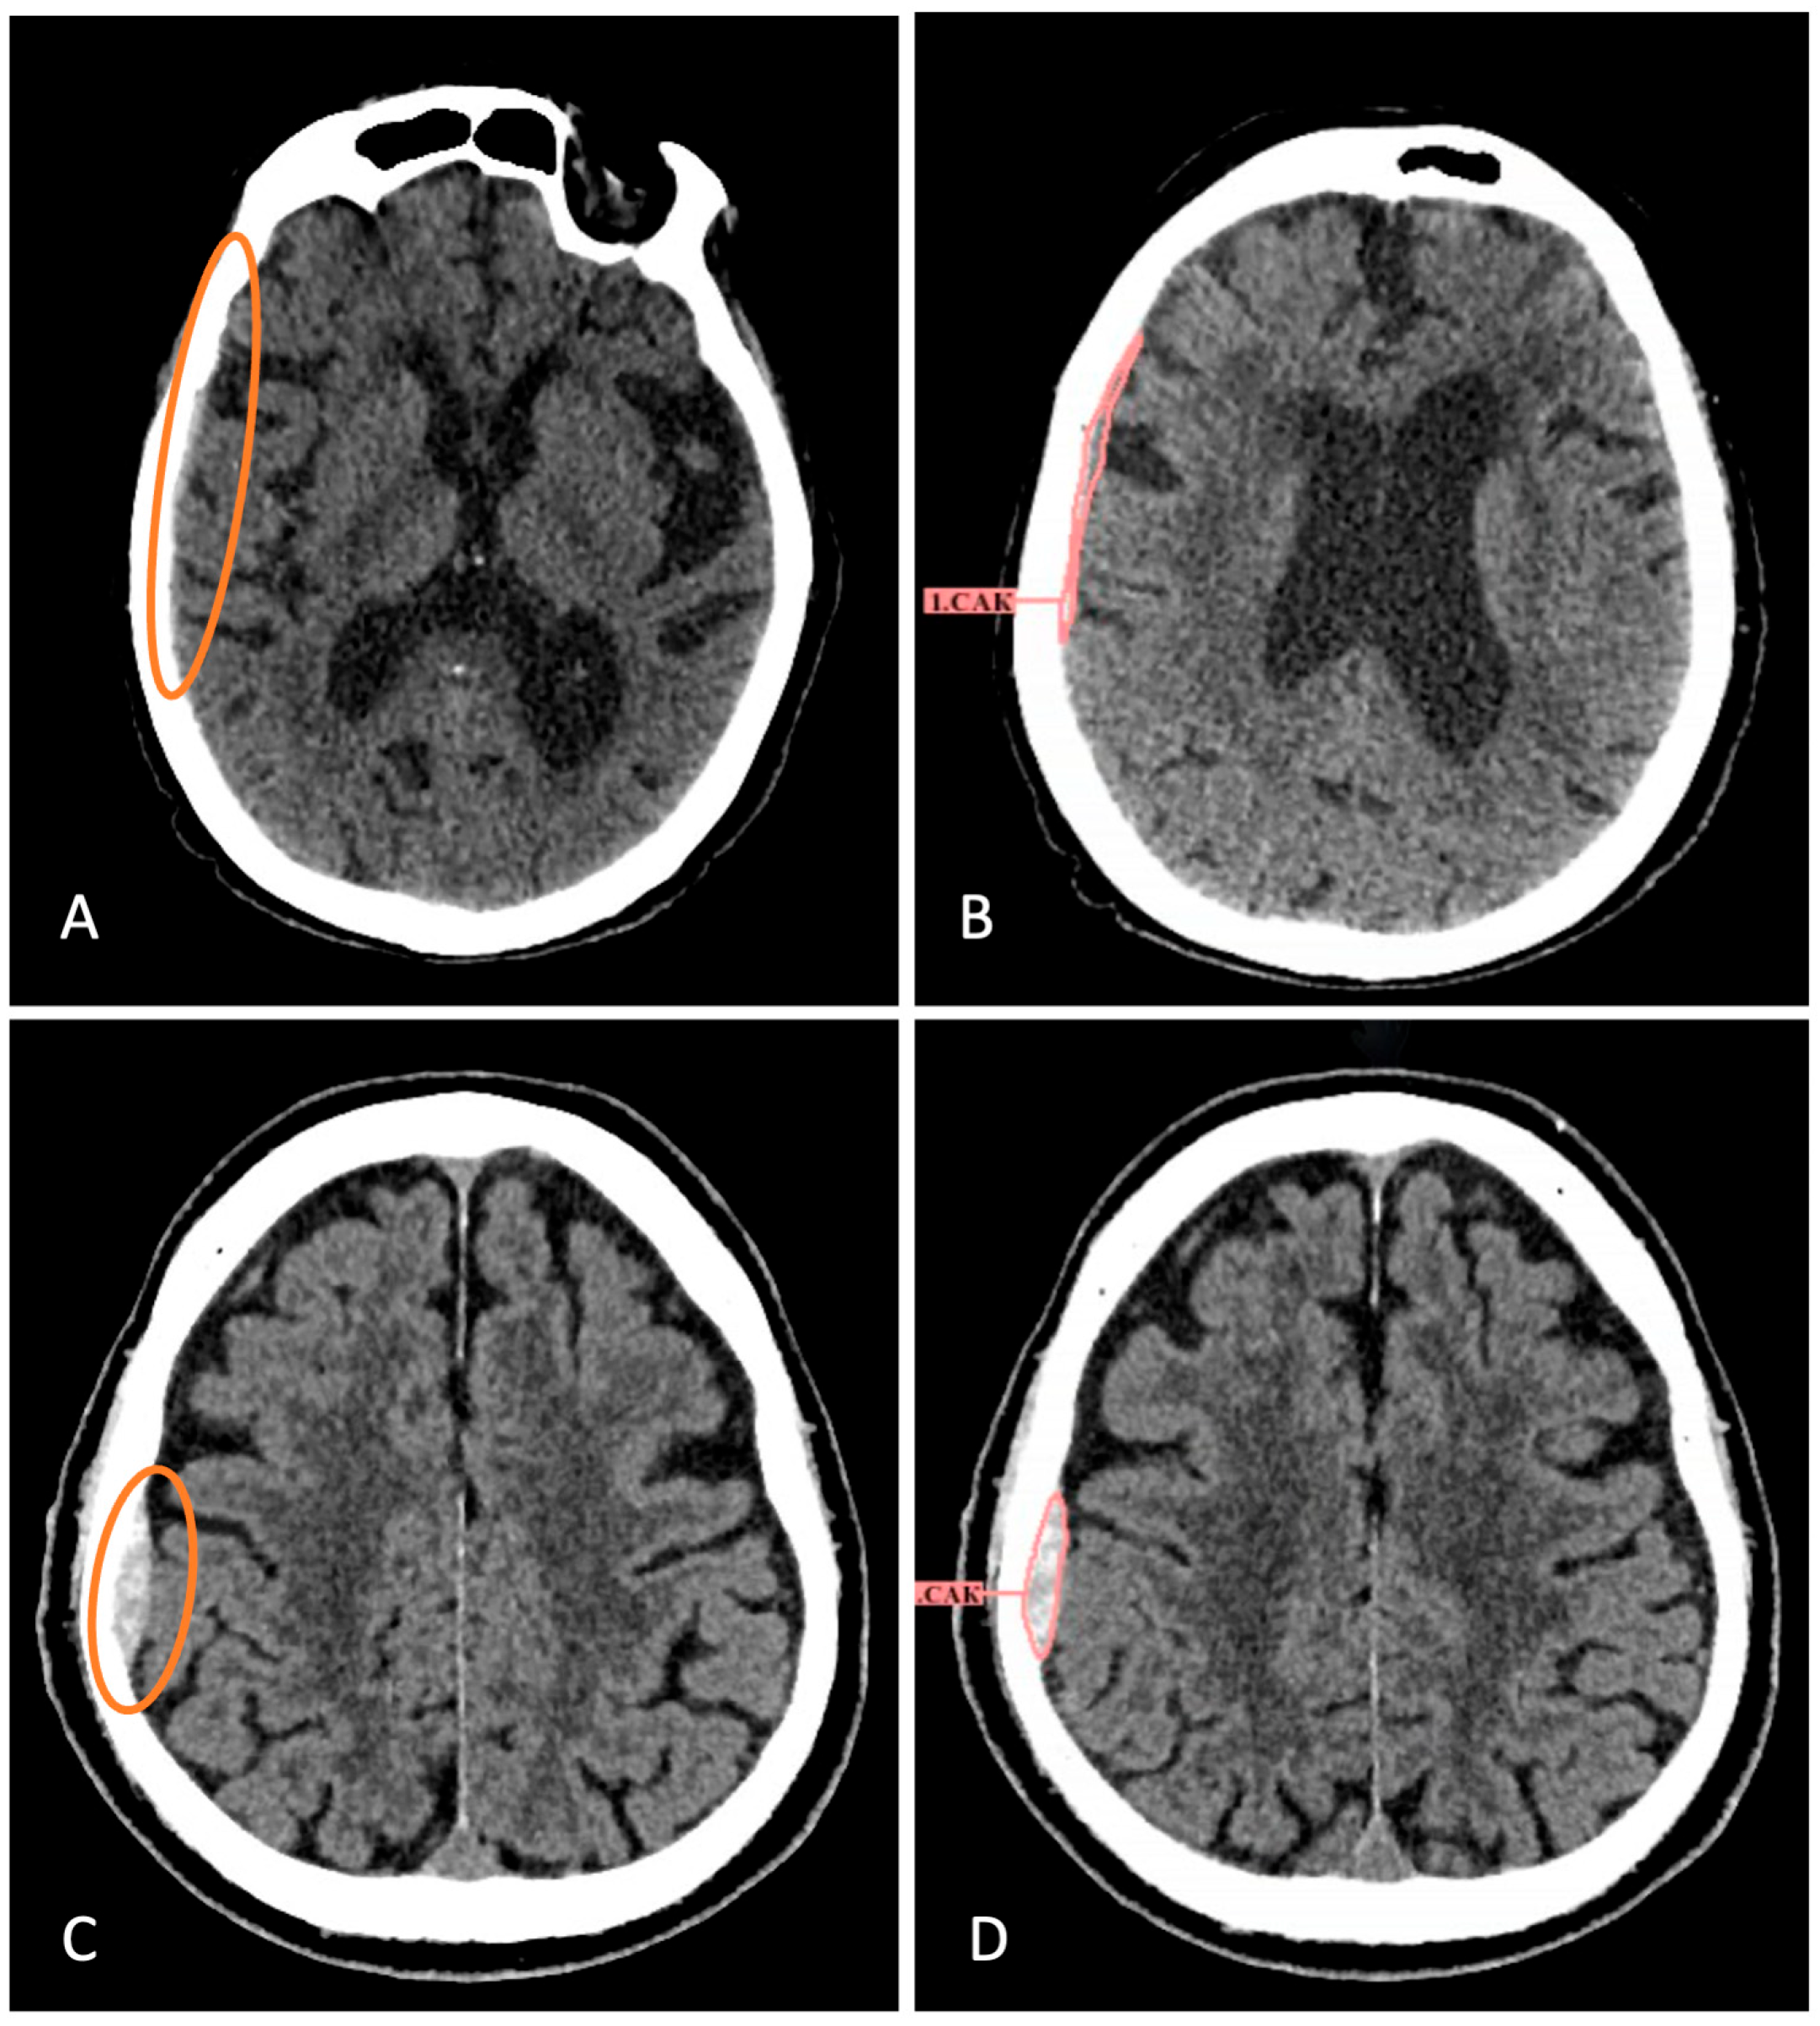

| 1 | 79F | SAH | Multiple regions | Small volume | Hypertensive crisis, fall | Subtle SAH signs |

| 2 | 21M | SAH | Parafalcine, tentorial | Small volume | Post-VPS surgery | Post-surgical changes |

| 3 | 63M | SAH | Tentorial | Small volume | Head trauma | Minimal bleeding |

| 4 | 71F | IPH | Parafalcine space | Small volume | Post-tumor resection | Surgical bed changes |

| 5 | 67M | Chronic SDH | Right fronto-parieto-occipital | Mixed density, 40 HU | Stroke workup | Chronic appearance |

| 6 | 45M | IPH | Right orbitofrontal | Small volume | Exclusion of acute intracranial pathology | Bone artifacts |

| 7 | 86F | SDH | Right temporo-parietal | Small volume | Syncope, atrial fibrillation | Small size |

| 8 | 81M | Chronic SDH | Bilateral | Mixed density, 39 HU | TIA symptoms | Chronic appearance |

| 9 | 67M | IVH + SAH | Left temporal horn, tentorial | Residual blood | Post-drainage | Probably due to haste, the pattern of hemorrhages was not described accurately enough |

| 10 | 90F | Hemorrhagic transformation | Ischemic zone | Petechial | Stroke progression | Ischemic mimicry |

| 11 | 45M | EDH | Right parietal | Small volume | Alcohol-related fall, radial fracture | Trauma history |

| 12 | 74F | Hemorrhagic transformation | Basal ganglia | Small volume | Hypertensive crisis | Early stroke phase |

Disclaimer/Publisher’s Note: The statements, opinions and data contained in all publications are solely those of the individual author(s) and contributor(s) and not of MDPI and/or the editor(s). MDPI and/or the editor(s) disclaim responsibility for any injury to people or property resulting from any ideas, methods, instructions or products referred to in the content. |